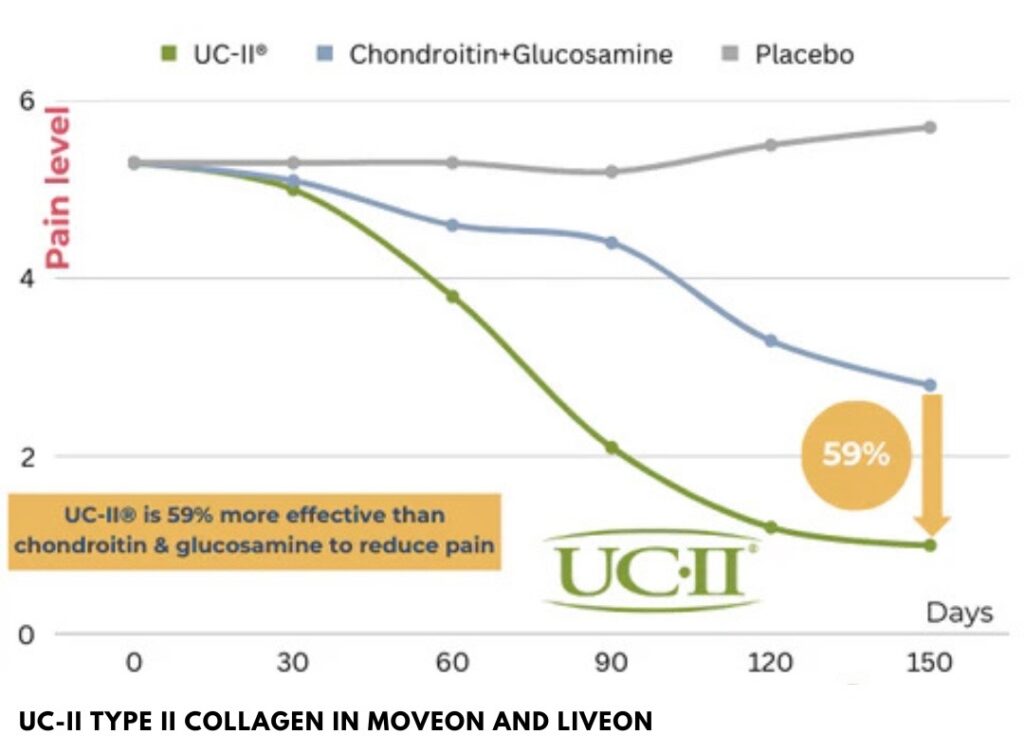

2x effective than Glucosamine & Chondroitin

A patented Type II Collagen, sourced from chicken cartilage from USA.

- Proven to be 2x more effective than glucosamine + chondroitin